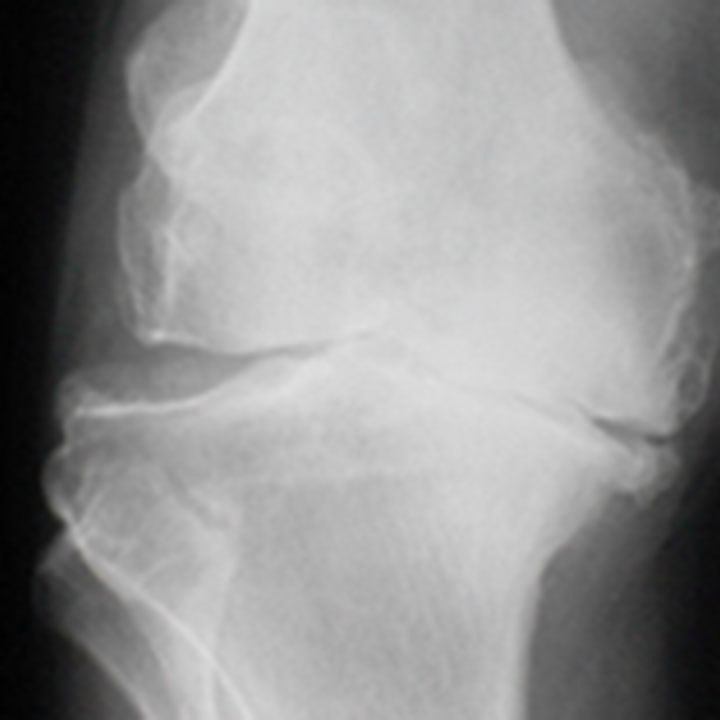

Slidgigt er den mest udbredte ledsygdom, der rammer stort set alle med alderen. Otte ud af ti har slidgigt, når de har passeret de 50 år. Slidgigt opstår, når brusken mellem knoglerne eftrhånden nedbrydes, og det er den mest almindelige årsag til, at der er behov for at indsætte en knæprotese.

De første symptomer er typisk smerter ved igangsætning, ømhed efter belastning og hævelse. Ved svær slidgigt opstår der ofte hvilesmerter, nedsat bevægelighed og måske fejlstilling i ledde.

Knæproteser anvendes også til personer med leddegigt, som forekommer hos cirka 1 % af den voksne danske befolkning. Kvinder rammes tre gange så hyppigt som mænd. Leddegigt er kendetegnet ved, at kroppens led bliver angrebet af en betændelseslignende tilstand. Sygdommen opstår hyppigst i 30 - 50 års alderen. I de fleste tilfælde medfører sygdommen, at leddene gradvist misdannes og dermed mister deres funktion. Det giver smerter ved bevægelse af leddene og deraf følgende indskrænket bevægelighed og stivhed i leddet.

Hvis du kun har slidgigt i det ene ledkammer - hyppigst på indersiden af knæet, anbelafer vi ofte en delprotese (Uniknæ). Dette er tilfældet for ca. 30 - 50% af alle patienter med slidgigt i knæet.